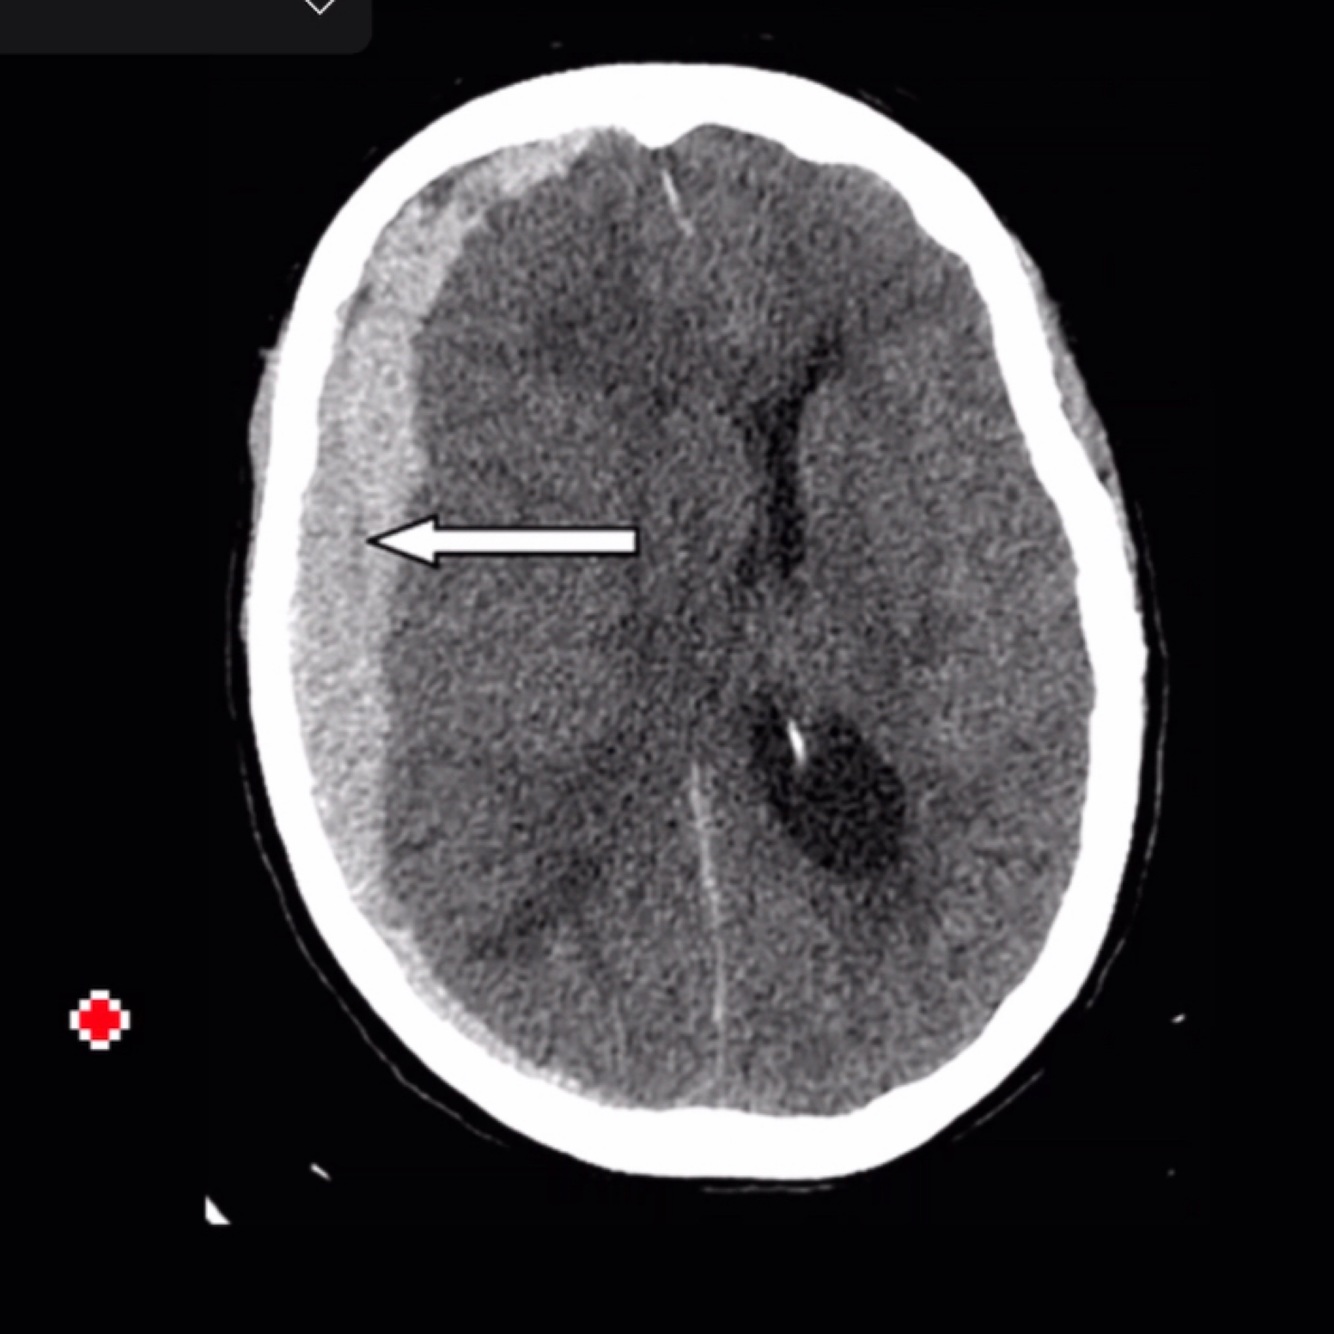

Q

Dx

A

Hematoma subdural